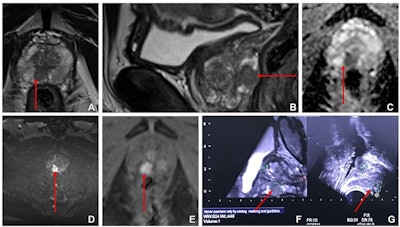

Pre-biopsy, multiparametric MRI can identify clinically significant prostate cancer and reduces unnecessary biopsies and the overdiagnosis of clinically insignificant disease, the team explained; the current prostate cancer workup protocol consists of this type of MRI exam combined with MRI-guided targeted biopsies.

The authors conducted a study that included 582 patients with suspected prostate cancer who underwent multiparametric MRI between January 2015 and August 2020. Of these, 413 had a PI-RADS score of at least 3 (intermediate -- and equivocal -- disease risk) and were randomized into either an intervention group that underwent ultrasound and MRI fusion-targeted biopsies with systematic random prostate biopsies (207, or 50.1%) or a control group which underwent systematic random biopsies alone (206, or 49.9%). The men underwent biopsy within a week after the multiparametric MRI exam.